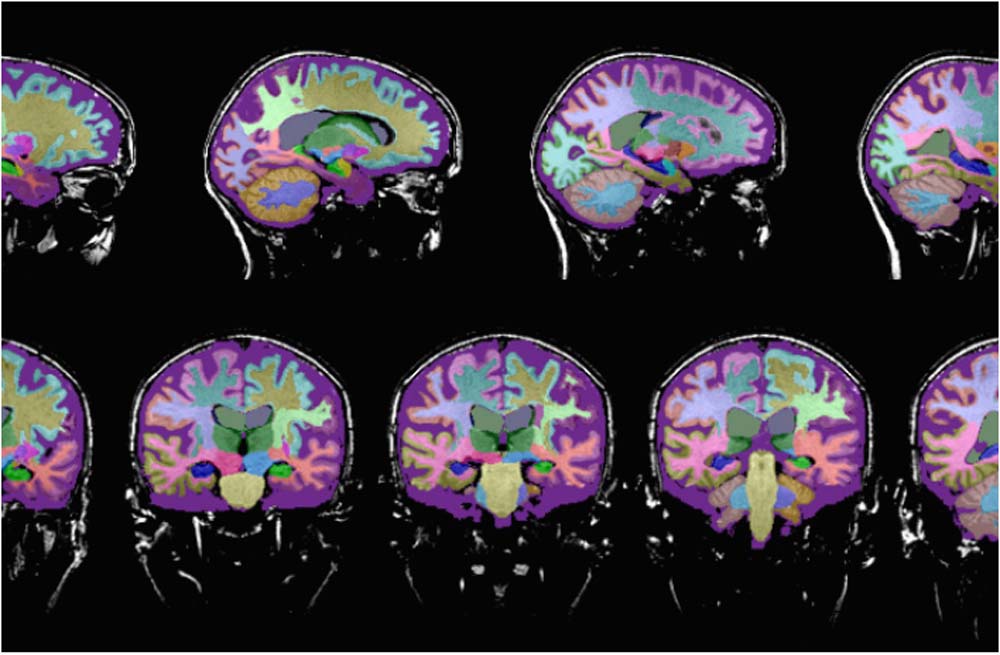

Neuroimaging is a critical tool for assessing the physical, structural and functional brain changes that occur in different parts of the brain during various neurodegenerative conditions.

- Structural imaging provides information about the shape, location and volume of brain tissue. Structural imaging techniques include computer tomography (CT) and magnetic resonance imaging (MRI).

Neuroreader™ is a computerized program that provides an assessment of total brain volume, hippocampal volume and volumetric data on different anatomical areas of the brain measured against a healthy database.